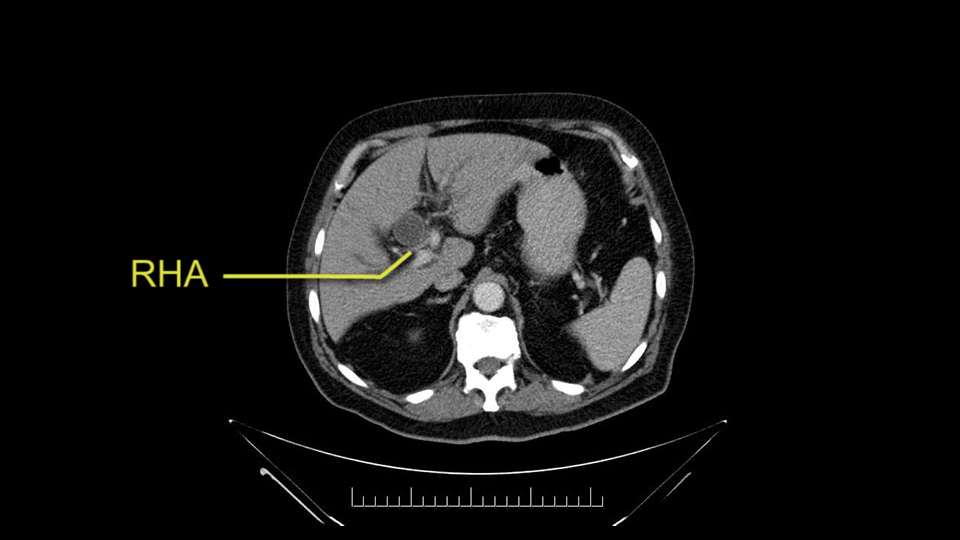

He has normal arterial anatomy: no accessory or replaced right hepatic artery, which is important because sometimes the right hepatic artery can come behind the neck of the pancreas and you have to be careful of that in a Whipple dissection.

Then you look for anomalies. The one you worry about the most doing a Whipple is a replaced or aberrant right hepatic artery coming off the SMA at its origin. So again, find the SMA. You can find it because the renal vein goes through it. Follow it up, up-up-up. Nothing coming off of there that I can see here. Nothing coming off of it, nothing coming off of it and just to confirm it, look at the celiac trfurcation. There’s the celiac, there’s the bifurcation, there's the splenic artery, hepatic artery. Make sure there’s a right, which there is here. The right usually goes under the bile duct: important when you’re going around the bile duct to do a Whipple. A replaced right goes under the portal vein and the bile duct way over here on the right. That’s about it.

The second point about the vascular anatomy-, is to again look for right hepatic arteries in the hilum, coming from the superior mesenteric artery by palpating-through the Winslow Hiatus. Usually we will check for a pulse in the posterior aspect of the hepatic hilum, where a right hepatic artery should not usually be found. In this case, the precaution is to avoid an accidental ligation of the right hepatic artery that might jeopardize perfusion of the right lobe, or if there is a completely replaced hepatic artery that can put the liver circulation at risk.

I am a believer in pylorus preservation. And in this case I see no reason why that wouldn't be possible. Mobilize the duodenum, divide the gastroepiploic vessels and divide the duodenum. I try to divide it with a linear stapler about four centimeters from the pylorus to have adequate length for my GI anastomosis. This facilitates exposure of the head neck of the pancreas. I find the gastroduodenal artery. This patient has normal arterial anatomy. Always on every preoperative CT scan I look to see if there is a replaced right hepatic. In this case I did not see one. Regardless of how confident I am I always look carefully for variant anatomy. I always do a clamp test on the GDA before ligation. I doubly ligate the GDA with not just a tie but a suture ligature because of the risk of GDA blowout in patients with a leak.